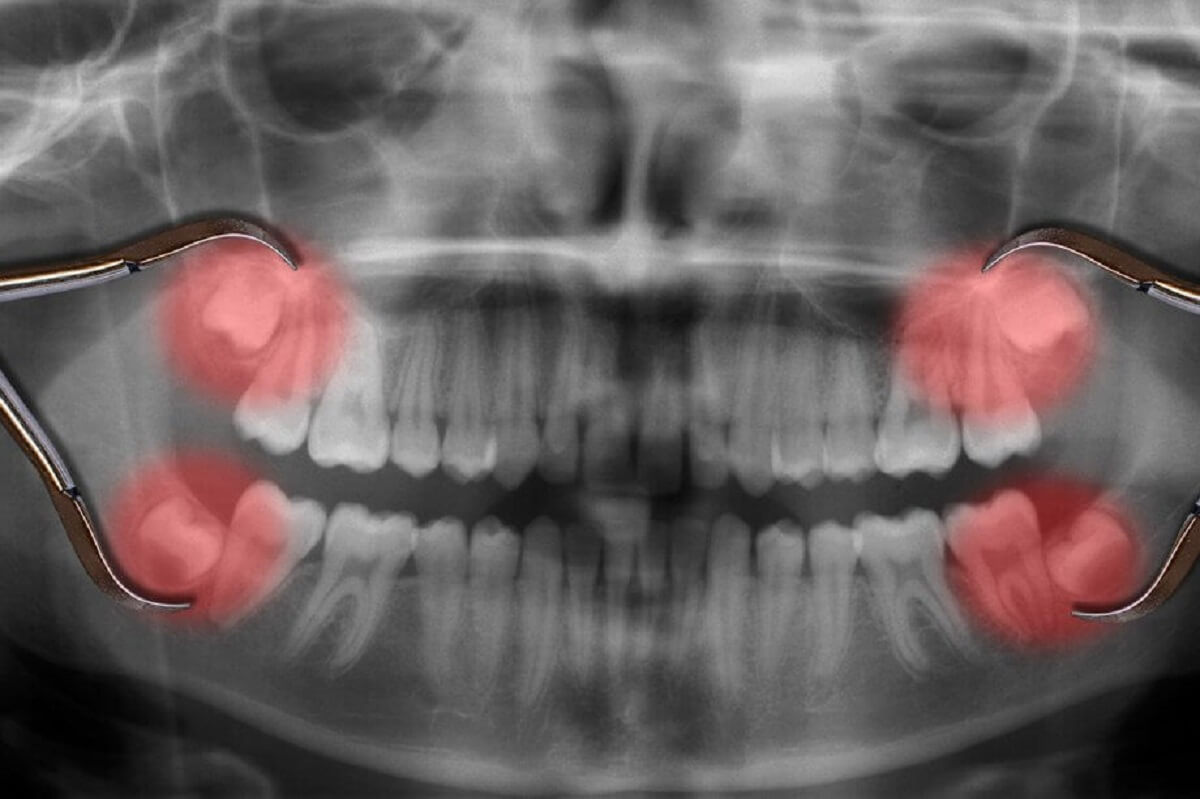

Some people wait until the teeth cause pressure, but early checks keep things simple. Imaging shows how the teeth sit and how much room they need. That gives the dentist a clear way to explain what comes next. A well-timed removal supports comfort and protects nearby teeth.